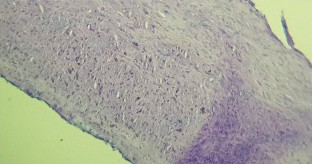

Fig. 2